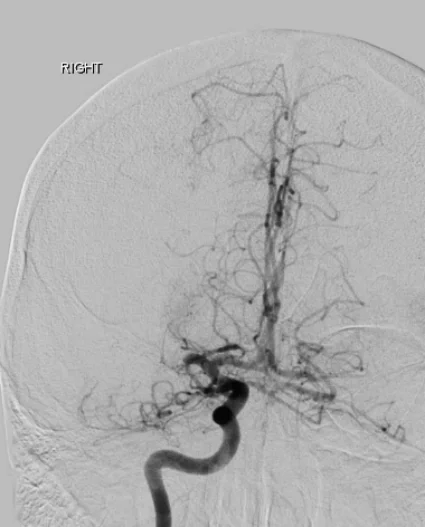

Lorsqu’une thrombectomie doit être réalisée, le patient est amené rapidement en salle d’angiographie et accueilli par l’équipe (paramédicaux, anesthésiste, neuroradiologue interventionnel(le)). En fonction de l’état de conscience, du confort et de la possibilité de rester immobile, la procédure est réalisée sous anesthésie locale ou générale. L’accès au réseau artériel se fait le plus souvent par l’artère fémorale au pli de la jambe ou l’artère radiale au poignet. Dans certaines situations, il est nécessaire d’accéder directement à l’artère carotide dans le cou. Une angiographie cérébrale est alors réalisée et permet de confirmer l’occlusion artérielle ou plus rarement de constater la recanalisation spontanée ou suite à la fibrinolyse intraveineuse. L’objectif est ensuite de naviguer un ou plusieurs cathéters au plus proche de l’occlusion voire au-delà afin d’essayer de retirer le caillot du corps soit en l’aspirant à travers un large cathéter, soit en le coinçant dans les mailles d’un stent qui est ensuite retiré du corps, soit par une combinaison des deux techniques. Plus rarement, en cas d’échec ou de constatation d’un rétrécissement structurel (sténose) de l’artère intracrânienne, à l’origine de l’occlusion, il est possible de dilater l’artère avec un petit ballonnet et éventuellement de laisser un stent en place. Lorsqu’un rétrécissement est constaté sur l’artère carotide dans le cou, il peut arriver que le même traitement (dilatation par ballonnet et mise en place d’un stent) soit nécessaire avant ou après la thrombectomie en elle-même, soit pour permettre le passage du matériel, soit pour éviter une récidive précoce. En fonction du type d’intervention, des médicaments antiagrégants peuvent être prescrits.